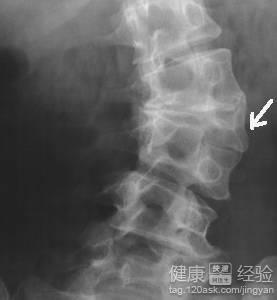

1這種症狀大多表現為脊椎後面有裂開的痕跡,椎間脊椎排列不整齊,骨盆不在原來的位置上,又或者脊椎的位置調換了等.但大部分外觀表現變化不大,而且輕微裂紋隱起來,不怎麼看的見,這種症狀大多在7歲以前明顯,過了七歲就會慢慢回歸正常,小孩尿床也明顯減輕了。

2如果7歲後還尿床大多數是與隱形脊柱裂沒有關系,因為假如說小孩到了6歲,再去檢查拍片,這種現象大大小小還是會有的,不會完全康復的,但是不要認為尿床真的與隱形脊柱裂有很大的關系,家長千萬不能認為這種病是不能治療的,不然會耽誤孩子的一生。